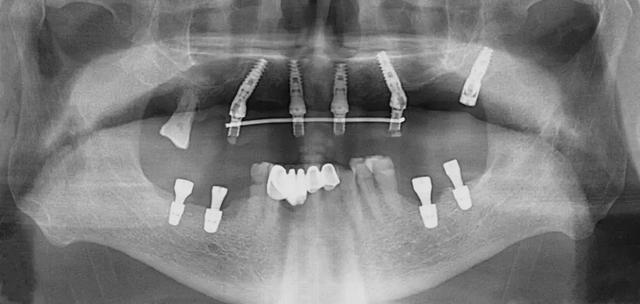

口腔科李德仁主任為老人仔細(xì)檢查了口腔情況,由于缺牙時(shí)間太久,牙床骨量極少,正常的種植修復(fù)需要植骨,手術(shù)創(chuàng)傷大而且半年后才能鑲牙吃飯。建議他進(jìn)行數(shù)字化導(dǎo)板種植,可以不用植骨而且當(dāng)天就能戴牙吃飯,手術(shù)簡(jiǎn)單,創(chuàng)傷小。老人和孩子很信任的接受了李主任的種植方案:上牙床種植5顆,下牙床種植4顆,當(dāng)天戴牙吃飯。

下午2點(diǎn)開始手術(shù),歷經(jīng)90分鐘,一共植入9顆種植體,全程。下午7點(diǎn)用了10多分鐘就完成了假牙安裝,假牙與牙床渾然一體,像是重新長(zhǎng)出的牙齒一般。

全口缺牙一日重建種植手術(shù)有以下優(yōu)點(diǎn):使用CT導(dǎo)板定位,在骨量好的位置種植,一般不需植骨,手術(shù)創(chuàng)傷小,手術(shù)時(shí)間短,愈合快,基本上沒有疼痛。拔牙同時(shí)種植牙,當(dāng)日戴臨時(shí)全口固定式假牙吃飯。